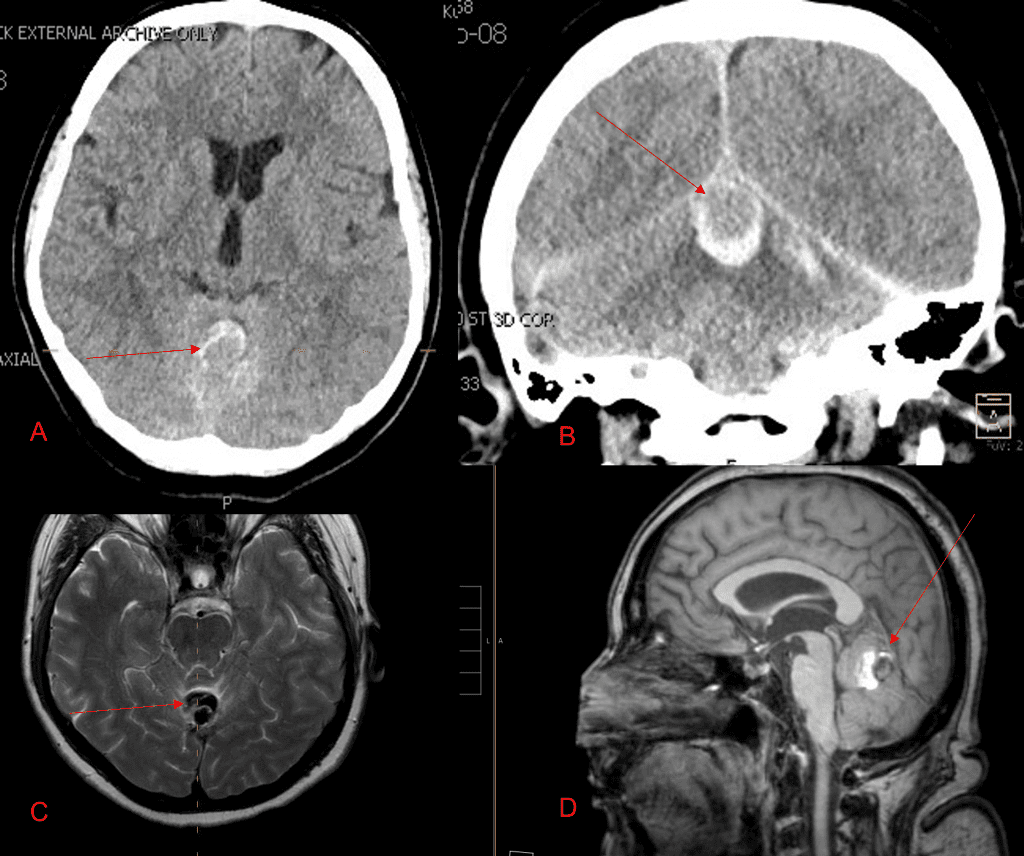

Over the 12 to 18 months, she continued to remain event-free and maintain her active independent lifestyle. Delayed angiography over that period confirmed complete obliteration of the Left ECA and Vertebral Artery shunts with near complete obliteration of the Right ECA shunts (Figure 7).

Figure 7. 12 mos follow-up angiograms confirm complete obliteration of the left ECA and Vertebral Supply to the AVM, with a small late-filling component from the right Occipital artery that is markedly Reduced in size and flow (top row). Near complete resolution of the aneurysm and hematoma Is observed on 16 mos post Gamma Knife MRI (bottom row).